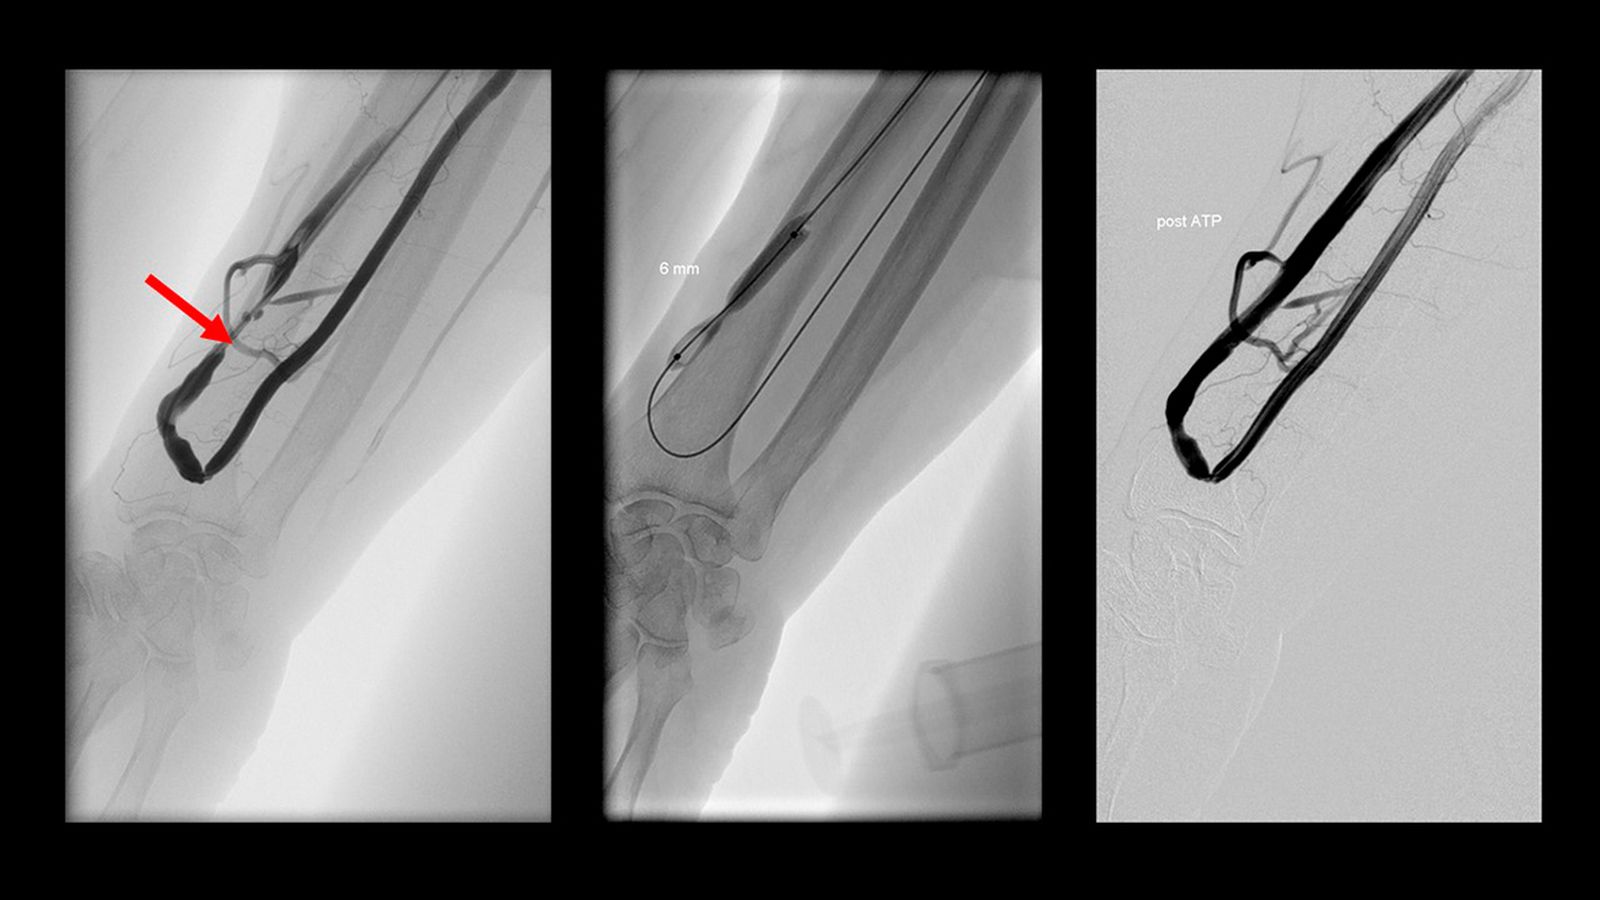

Imagen radiológica antes, durante y después del tratamiento de la estrechez de una fístula de un paciente en la Sala de Radiología Vascular del Hospital Universitario Juan Ramón Jiménez.

Imagen radiológica antes, durante y después del tratamiento de la estrechez de una fístula de un paciente en la Sala de Radiología Vascular del Hospital Universitario Juan Ramón Jiménez. / M. G.

Por ello, muchos profesionales sanitarios vigilan las fístulas para evitar que esto ocurra y cuando encuentran un estrechamiento la tratan antes de que la fístula se pare. Una de las formas de tratarlas es mediante la apertura de la estrechez con unos pequeños globos o balones que son introducidos por pequeños orificios. Dichos tratamientos son muy efectivos y llevan años realizándose en Huelva por parte del Unidad de Radiología Vascular Intervencionista del Hospital Universitario Juan Ramón Jiménez con muy buenos resultados.